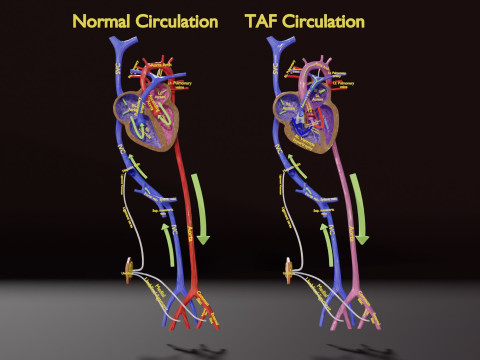

The model meshes include adult circulation versus circulation in Tetralogy of Fallot (TAF), arrow labels and text labels. The blood flow in a patient with Tetralogy of Fallot is outlined in this model. To contrast it to normal blood circulation a separate model of normal circulation is included. The Tetralogy of Fallot (OVER RIDING OF AORTA, PUL STENOSIS, VENTRICULAR SEPTAL DEFECT, RIGHT VENTRICULAR HYPERTROPHY), fossa, ligament teres , venosus, and arteriosus are duly depicted with proper labelling and blood flow directional arrows. Excellent model for teaching, demonstration and knowlegde of human body. The models include both procedural and image textures blend files separately. The texture file include diffuse, roughness and normal png and jpeg based on non overlapping UV maps.